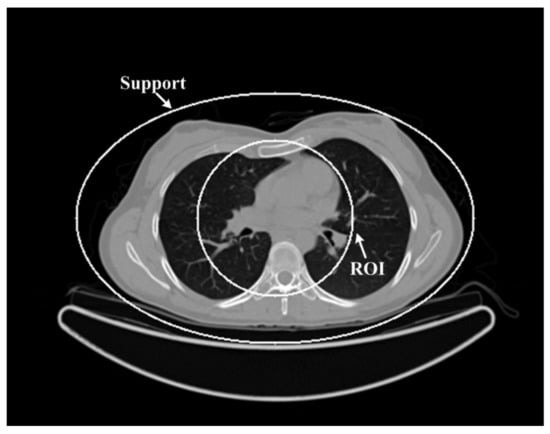

3.2. Real CT Projection

A sheep chest was scanned with both normal (100 kV, 150 mAs) and low-dose (80 kV, 17 mAs) protocols on a SIEMENS Somatom Sensation 64-Slice CT Scanner using a circular cone-beam scanning mode. The sinogram of the central slices was extracted, which is fan-beam geometry. The radius of the trajectory was 57 cm. The 1160 projections were uniformly collected over a 360° range. For each projection, 672 detector elements were equi-angularly distributed to define a field of view (FOV) of 50.1 cm in diameter. We first reconstructed the global data of a goat lung at normal dose and low dose using the algorithm in the literature [19]; the reconstructed image was 768 × 768 pixels, the actual size was 43.63 cm × 43.63 cm, and we used this reconstructed image as the reference image. Then, we selected the area with a 61 pixels radius as the ROI. Finally, only the projection data through the ROI were kept, and the truncated projection data were obtained only through the ROI. The selected ROI is shown in Figure 4.

Figure 4.

Reconstructed images from real CT projection data: (a) Normal dose; (b) low dose. The display window is [−700 800]HU.